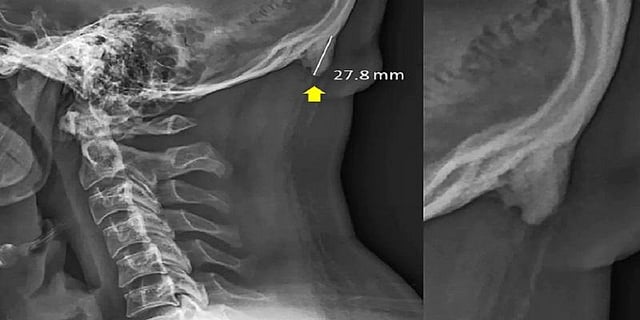

செல்போனை அதிக நேரம் குனிந்தபடியே பயன்படுத்தி வருவதால் தலையின் பின்புறம் உள்ள மண்டை ஓட்டுக்குள் கொம்பு போன்ற கூர்மையான எலும்பு ஒன்று வளர்வதாக விஞ்ஞானிகள் கண்டுபிடித்துள்ளனர்.

செல்போனை அதிக நேரம் குனிந்தபடியே பயன்படுத்தி வருவதால் தலையின் பின்புறம் உள்ள மண்டை ஓட்டுக்குள் கூர்மையான எலும்பு ஒன்று வளர்வதாக  விஞ்ஞானிகள் கண்டுபிடித்துள்ளனர். இது தொடர்பாக தெரிவித்துள்ள விஞ்ஞானிகள், அதிக நேரம் குனிந்தபடியே பயன்படுத்துவதால் தலையின் முழு எடையும் மண்டை ஓட்டின் பின்புறம் செல்கிறது.

இதனால் தசை நாண்கள், தசை நார்கள் வளர்கின்றன. இதன் காரணமாக தலையின் பின்புறம் உள்ள மண்டை ஓட்டுக்குள் கூர்மையான எலும்பு ஒன்று வளர்கிறது என்று தெரிவித்துள்ளனர்.